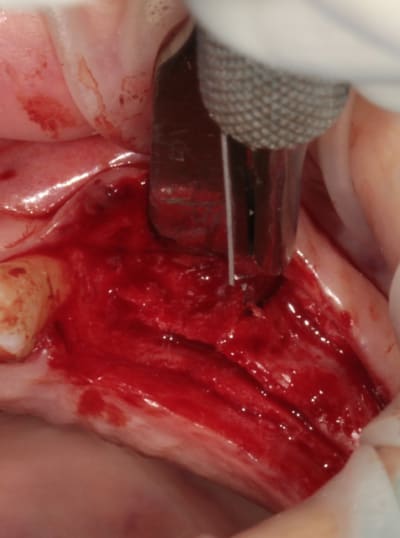

4:

évolution

Tatum D1